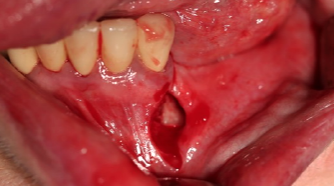

У данной категории пациентов не только отсутствовала необходимость создания в полости рта второй операционной зоны для забора трансплантата, но и благодаря проведению операции «туннельным» способом, позволило сократить длину линии разреза (рис.5)  и следовательно значительно уменьшить операционную травму пациента.